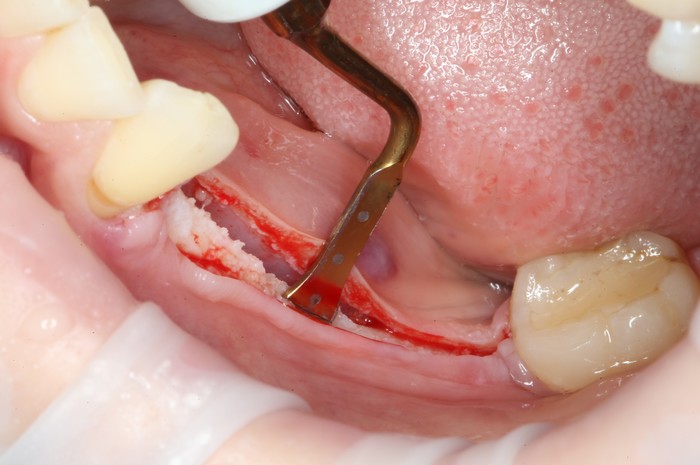

На верхней челюсти было дополнительно удалено два боковых резца с одномоментной установкой имплантатов, так же они были установлены в области четверок и шестых зубов. Дополнительно было проведено наращивание костной ткани - двусторонний синус - лифтинг. О том, что это такое, можно почитать ТУТ и ТУТ.

После нехитрых манипуляций мы прощаемся с Русланом на 4 месяца.

Этого времени достаточно на приживление имплантатов.